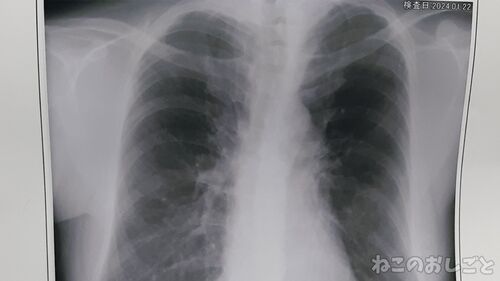

【風邪症状はまだ隔離】咳が止まらないから病院へ行って血液検査やらレントゲンやら・・・

体調悪いからスタート うーん体調が悪いです! 今年は地震から始まって体調崩して それがズルズル続いてる感じで なんともスッキリしない! なのにもう今日22日ですよ? もうすぐ1月が終わってします! 早くなぁーい? こっわ! 流石に病院行ってきた! でさ…